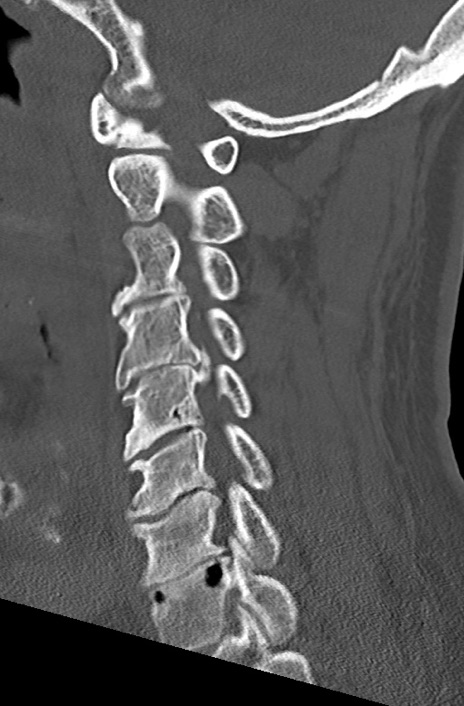

頚椎CT

矢状断像と横断像